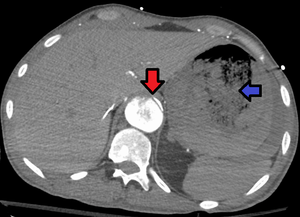

Aorto enteric fistula and aortic dissection of the thoracic aorta. Arrow shows the flap in the aorta. Heterogeneity is blood in the stomach | |

An aortoenteric fistula is a connection between the aorta and the intestines, stomach, or esophageus.[1] There can be significant blood loss into the intestines resulting in bloody stool and death.[1] It is usually secondary to an abdominal aortic aneurysm repair.

Diagnosis is typically via a CT angiography, esophagogastroduodenoscopy, or arteriography.[1] It is part of the differential diagnosis of gastrointestinal bleeding.[2]